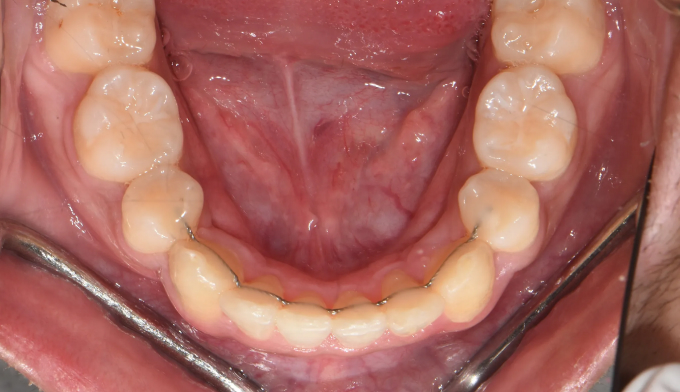

이번 케이스도 뒤늦게 송곳니가 덧니로 나오는것을 확인하고 치아교정을 하고자 내원한 중학생입니다.

부족한 공간이 꽤 많고, 입도 돌출되어 보여서 어쩔수 없이 발치교정을 계획하였습니다.

총 치료기간은 23개월입니다.